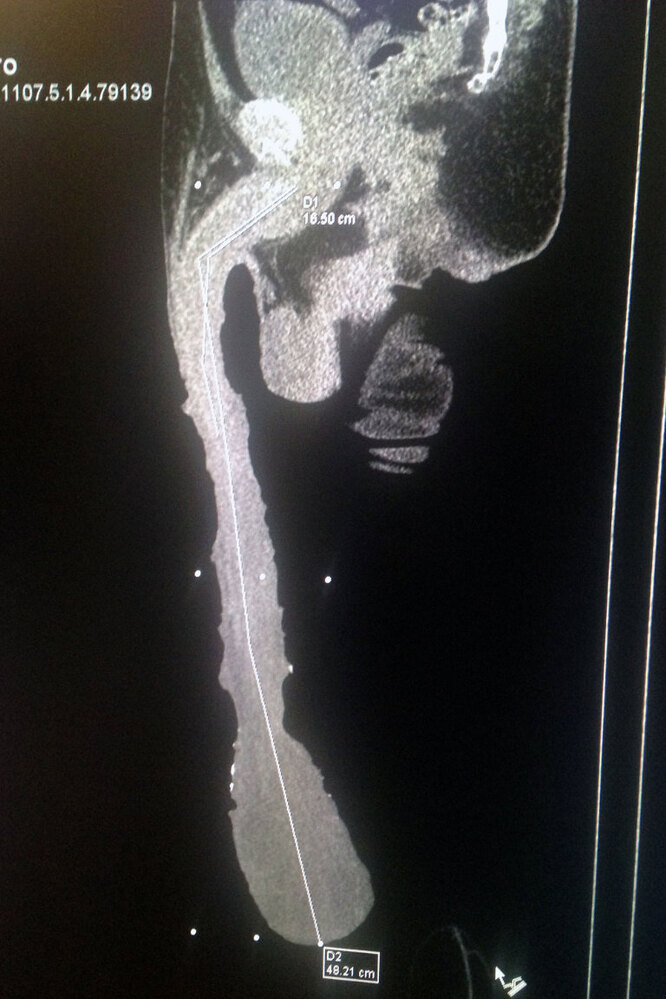

Мексиканцу Роберто Эскивелю Кабрера 54 года, он живет в небольшом городке Салтийо и претендует на попадание в “Книгу рекордов Гиннесса” как обладатель самого большого пениса на планете - 48,21 см (18,9 дюймов). Уберите от экрана детей и впечатлительных взрослых, внутри откровенные фотографии (пусть и с некоторыми купюрами)! Можно подумать, на что только не пойдет человек ради сенсации. Тем, кто не верит, Роберто показывает снимок с рентгеновского исследования. Длина тела его пениса - около 18 сантиметров, остальные 30 - крайняя плоть. Да, она немного превышает привычные размеры! Для интересующихся цифрами: длина окружности его пениса - 25 сантиметров, вес - около 900 граммов. Он может похлопать себя членом по носу (теперь ты тоже не сможешь об этом забыть!). Кабрера всегда “одевает” свое достоинство, потому что ему так удобно, и оголяет его только на приеме у врача, да и то неохотно. Мужчина претендует на запись в “Книге рекордов Гиннесса”, но в ней пока нет такой номинации. Впрочем,

Можно подумать, на что только не пойдет человек ради сенсации. Тем, кто не верит, Роберто показывает снимок с рентгеновского исследования. Длина тела его пениса - около 18 сантиметров, остальные 30 - крайняя плоть. Да, она немного превышает привычные размеры!

Для интересующихся цифрами: длина окружности его пениса - 25 сантиметров, вес - около 900 граммов. Он может похлопать себя членом по носу (теперь ты тоже не сможешь об этом забыть!).